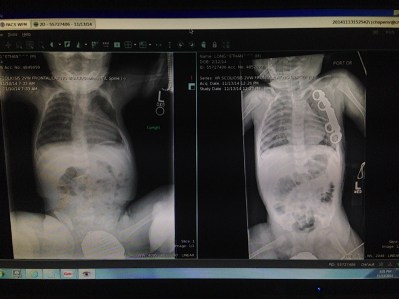

My husband and I noticed Carson’s spine appeared to be curved when he was just 5 months old. I brought up our concerns to his pediatrician at his 6 month appointment. She dismissed our concerns, saying babies are just flexible and they don’t have very strong muscles to hold themselves properly. When Carson was 10 months, he was having testing done for another medical condition. During that test my husband asked the radiologist to shoot a film of his spine because we were so certain he had scoliosis….and there it was…a very obvious “s” shaped curve, 60 degrees thoracic and 45 degree lumber. With that we started our research.

He wore that brace until September 24, 2013, his surgery day, just 1 month after turning 2. The plan was to remove the hemivertebrae and fuse L4 and L5. The total OR time was to be about 3 hours. Everything went smoothly with his surgery. His curves decrease to 48 degrees thoracic and 38 degrees lumbar. We saw him in PACU at about noon that day. He was screaming and in a lot of pain. The next 48 hours where the worst days I have ever experienced.

Michael had his first post x-ray at about 6 weeks after surgery. It was amazing to see the difference. He actually gained 2 inches in height when he came home from surgery. This x-ray was the first time we could see his 2 rods and 20 screws. Even though the plan wasn’t to straighten his spine, his back looked great. The compensating curve did not compensate back as hoped so he has a 38* curve on his hip that has stayed consistent.